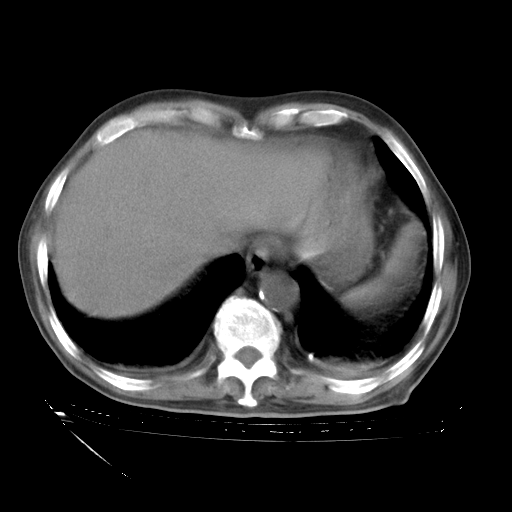

甲强龙80mg/日+抗结核治疗(异烟肼+利福霉素+乙胺丁醇)10天。复查肺部CT。

治疗10天肺部CT

94186 3 1 .bmp

94186 3 2 .bmp

94186 3 3 .bmp

94186 3 4 .bmp

94186 3 5 .bmp

94186 3 6 .bmp

94186 3 7 .bmp

94186 3 8 .bmp

94186 3 9 .bmp